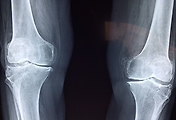

슬개골(무릎뼈)은 무릎 관절의 앞쪽에 위치해 무릎을 보호하고, 다리의 움직임이 부드럽게 이루어지도록 돕는 중요한 뼈입니다. 하지만 여러 요인으로 인해 이 슬개골이 제 위치에서 벗어나 탈구되는 경우가 있습니다.

슬개골 탈구는 통증과 함께 무릎 기능을 저하시켜 일상생활에 큰 불편을 초래하죠. 그렇다면 슬개골 탈구는 왜 생기는 걸까요? 오늘은 슬개골 탈구의 주요 원인을 자세히 알아보겠습니다.